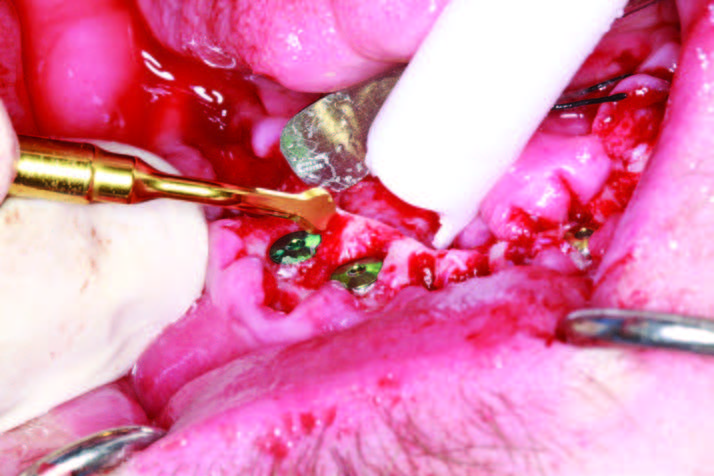

After assessing the patient’s vitals and performing sterile protocol to include a Salvin Split Drape (Salvin Dental Specialties), a facial scrub, and oral chlorhexidine rinses, the patient was anesthetized and extractions were done (Physics Forceps [Golden- Dent]). Piezosurgery (mectron) was also used to sever periodontal ligaments, clean sockets, and level and smooth bone. Physics Forceps are unique surgical forceps that use the alveolar bone as a fulcrum so the tooth can be atraumatically rotated out of the socket. The beaks of the forceps engage the lingual or buccal cervical area and, with a gentle rotating motion, the tooth is released from the periodontal ligament and then removed with traditional forceps (Figures 4a and 4b).

If the tooth is ankylosed or multi-rooted, then a Piezo surgical device is used to sever the periodontal ligaments (Figure 4c). It uses micro vibrations to allow the various inserts to remove bone, cut ligaments, and level osteotomies with a minimum of bleeding. It practically stops bleeding due to the movement of bone, the sealing of capillaries, and saline irrigation during the procedure. Extractions of all the mandibular teeth were done, and a caliper was used as measured in the reformatted CBCT scan (3DDX) to mark the alveolus and begin osteoplasty at each socket for the planned implant platform placement (Figure 5a). The osteoplasty was performed atraumatically using the Piezosurgery unit, and, after a cut was made buccal to lingual, a diamond insert was used to smooth all sharp edges and to level the implant sites using the Piezo surgical device (Figures 5b and 5c). A 10,600-nm CO2 laser (LightScalpel) was used to disinfect the sockets (Figure 6a). The laser uses water as its main chromophore and removes tissue by vaporization while limiting any zone of necrosis. Bacterial kill within the extraction socket, granuloma removal, and hemostasis are all accomplished with the use of this true spatially accurate laser device. In fact, use of the laser to trim tissue around abutments and permucosal healing abutments, treat peri-implantitis, and remove frena to decrease tissue pull on implants are all indicated procedures for this wavelength of CO2 laser.[3] Trimming of hypertrophic tissue during maxillary provisional placement allows for tissue modification without bleeding (Figure 6b).